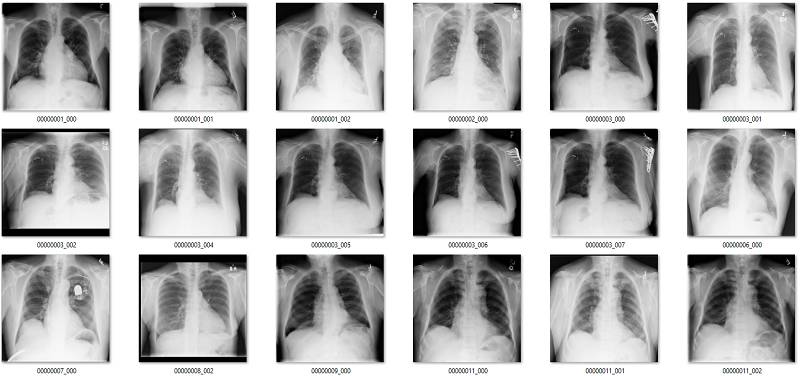

这部分要说该数据集中基于标签的图像。它们是随机选取包含 18 张图像的序列集,并非精挑细选。

我尽量保持谨慎,当一个案例模棱两可的时候,我选择标出标签类别。在所有图像中,红色 = 明显错误的标签;橙色 = 怀疑态度,我没有指出这个问题,但是不能排除这种怀疑。(出于临床诊断的习惯 :p)

肺不张(Atelectasis)